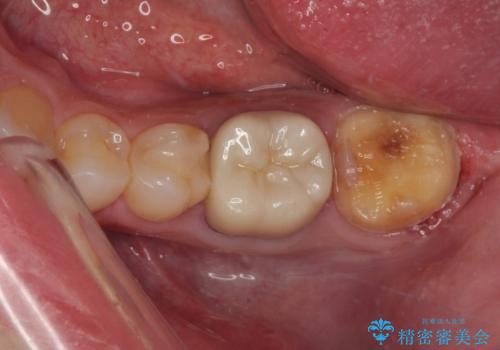

- 詰め物が欠けたとのことで来院された患者様です。来院時特に症状もなく神経の生活反応も確認できました。

詰め物の範囲が大きいためフルジルコニアクラウンによる補綴治療を行いました。

拡大鏡視野下で詰め物、虫歯を除去しフルジルコニアクラウンに適切な形に整えました。